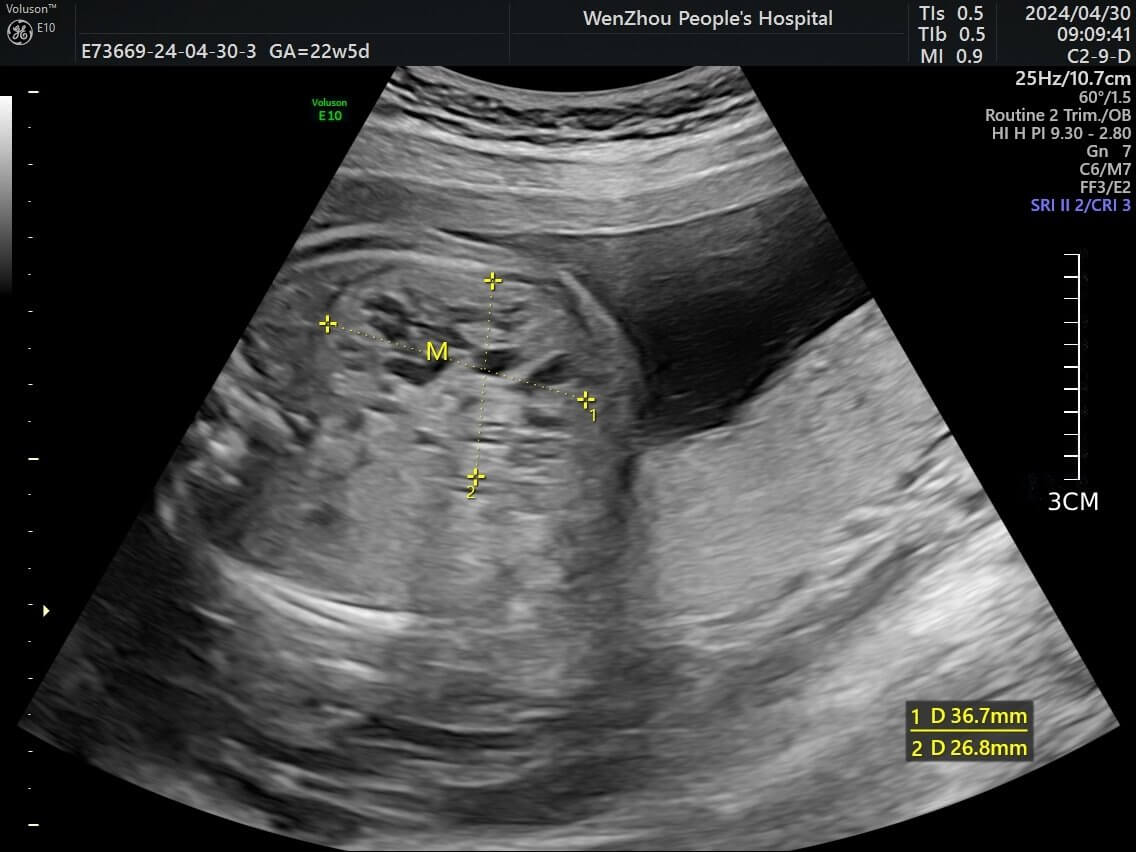

At 22+5 weeks, targeted fetal ultrasound demonstrated a mixed-echogenic lesion

in the right hepatic lobe measuring 27

Fig. 1.

Fetal ultrasound image demonstrating a dendritic pattern at the intersection of yellow dashed lines within the right lobe of the liver. Image is de-identified.